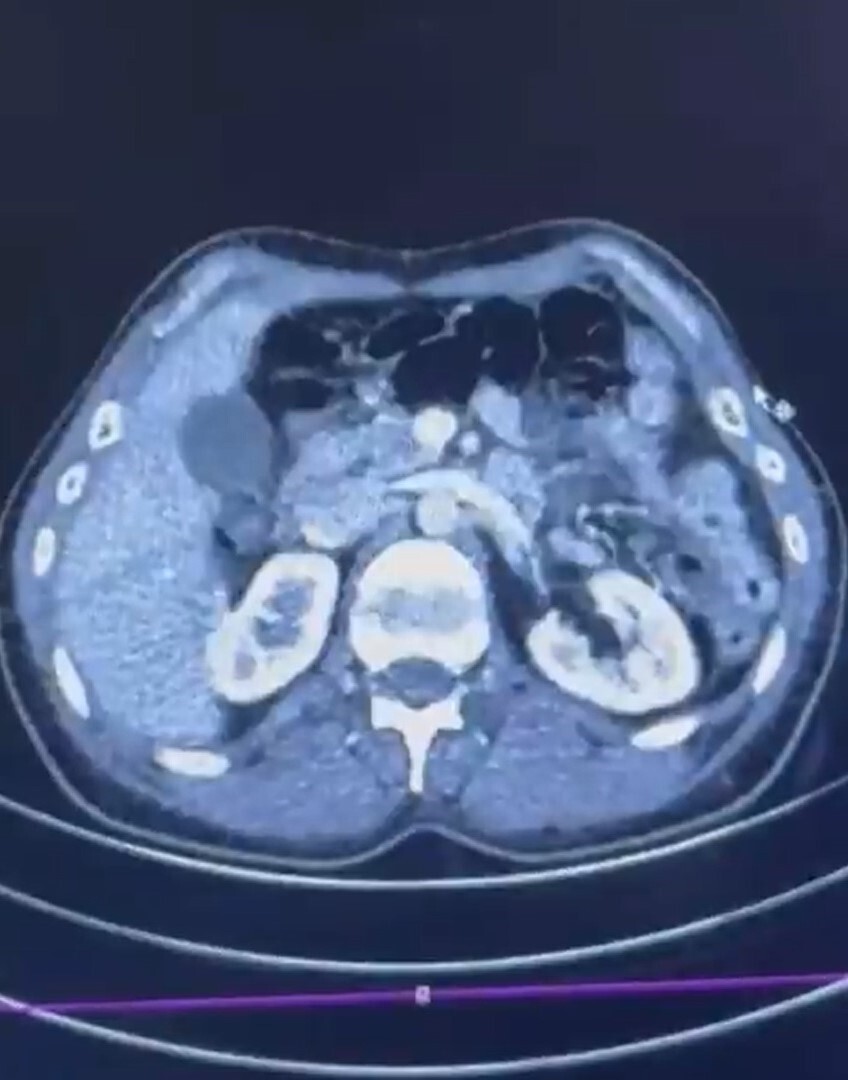

Kayseri Şehir Hastanesi'nde yapılan iç beden muayenelerinde, S.C. ve R.B.C. isimli şahısların mide kısımlarında toplam 50 adet kapsül şeklinde toplamda 554 gram uyuşturucu madde bulundu.

ŞÜPHELİLERİN MİDESİNDE KAPSÜL ŞEKLİNDE YARIM KİLO UYUŞTURUCU MADDE ELE GEÇİRİLDİ.